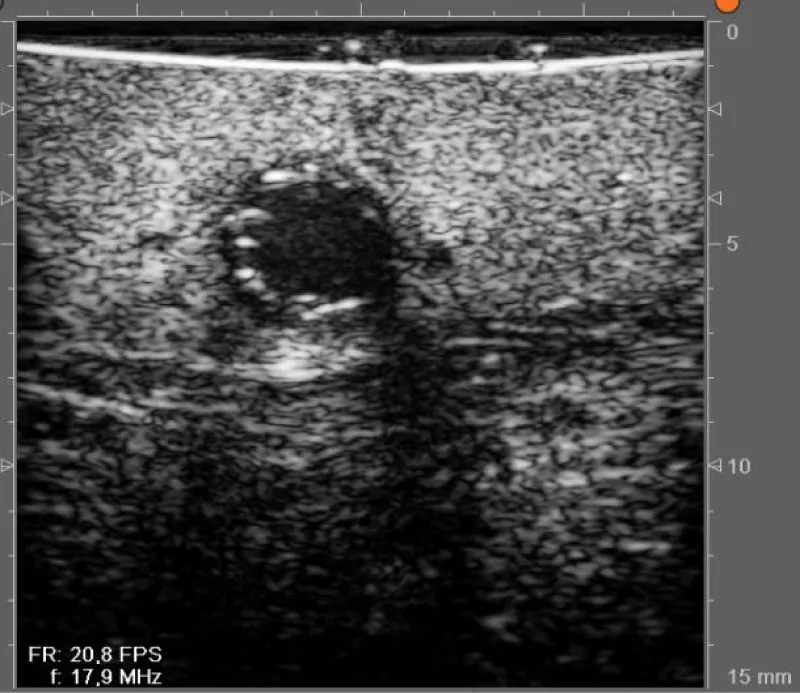

In case of doubt about the quality of the anastomosis (due to technical challenges during the realization of the anastomosis, or obtainment of nonideal PI values), we can assess the result of the anastomosis with the epicardic echography (Figures 12,13):

Figure 12: Echographic evaluation of an anastomosis between the left internal mammary artery and the left anterior descending artery.

Download Image

Figure 13: Doppler echographic evaluation of an anastomosis between the left internal mammary artery and the left anterior descending artery.